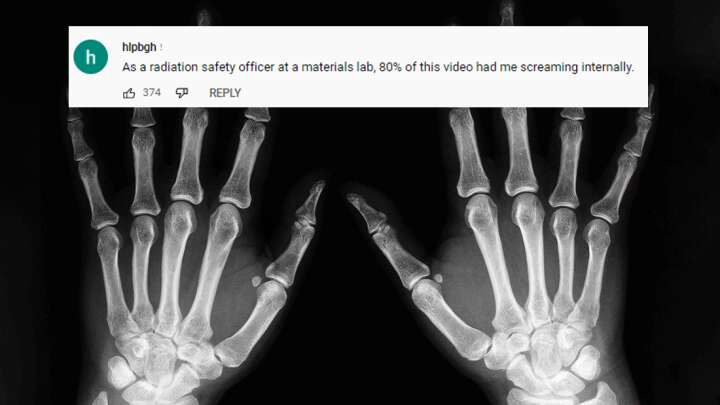

这台廉价的x光机及其结果得到了不同放射科医生的混合反应。迈克尔·切利尼(Michael Cellini)博士赞扬了奥斯曼在家中制造一台机器的努力,尽管所产生的图像无法提供可靠的诊断。然而,当奥斯曼决定用自己的手测试机器时,切利尼博士并不觉得好笑,他说:“产生的x光并不像CT扫描那么糟糕,但这并不意味着你应该这样做。”与此同时,视频中的一些评论感叹这不是一个非常明智的想法,其中一人写道,“作为材料实验室的辐射安全官员,这段视频有80%的时间让我内心尖叫。”